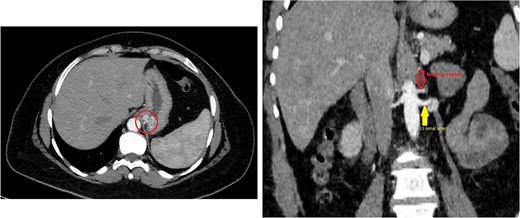

The CT scan confirmed a Dieulafoy’s lesion from the left phrenic artery (Fig. 2a and b) and showed collateral vascular channels around the pancreas with near-complete celiac trunk compression by the median arcuate ligament (Fig. 3). She underwent left phrenic artery embolization without complications, while asymptomatic celiac artery compression was treated conservatively. A follow-up endoscopy showed no bleeding or ulcers (Fig. 1d). Later, she developed severe left flank pain, and a contrast-CT revealed splenic vein thrombosis with infarction (Fig. 4), which was treated conservatively. Additionally, an incidental finding of left pleural effusion was drained. Rising inflammatory markers were managed with analgesics and IV antibiotics. She was discharged with outpatient follow-up, and at her 10-day visit, she reported improvement, stable hemoglobin, and normal inflammatory markers. She was satisfied, and a follow-up endoscopy was planned in 2 weeks.

Sagittal abdominal CT angio shows complete obliteration of the celiac trunk due to compression from the medical arcuate ligament.

Endoscopic treatments for Dieulafoy lesions include thermal (heat probe, argon plasma), injection (epinephrine, norepinephrine), and mechanical methods (banding, hemoclips), often combined for better outcomes [2]. If these methods fail, selective arterial embolization can be used as an alternative, involving angiography to identify the bleeding artery, which is then embolized with glue or coils [5]. Surgical intervention remains a final option with a high success rate for refractory cases [4]. The CT scan, in this case, confirmed a Dieulafoy’s lesion from the left phrenic artery, treated with embolization, and showed near-complete celiac trunk compression by the median arcuate ligament, treated conservatively. Median arcuate ligament syndrome (MALS) is a rare condition affecting 2 in 100 000, caused by celiac artery compression. It may have genetic and environmental causes and presents with bloating, weight loss, nausea, vomiting, and abdominal pain [6]. MRA and Doppler ultrasound are useful, but CTA is preferred for its detailed images, despite radiation and contrast risks [6]. MALS leads to significant hemodynamic changes, potentially causing pancreaticoduodenal aneurysms, splenic infarction, and splenic vein thrombosis due to reduced celiac artery flow. Severe compression can result in mesenteric ischemia and visceral infarction, with the spleen being especially vulnerable [7]. Treatment of MALS involves surgically decompressing the celiac artery. Minimally invasive methods generally result in faster recovery and less pain but have their risks. If stenosis persists, additional procedures like stenting may be necessary [6, 8].